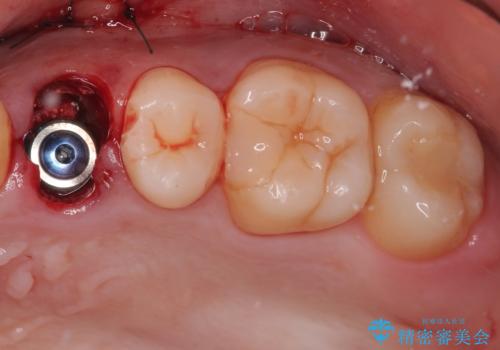

- 以前他院で、左上小臼歯(前から4番目)の虫歯治療を受けた患者様が、歯の根元から歯が折れてしまったことを主訴に来院されました。

他院では「抜歯が必要」と診断されており、「どうせ抜歯になるなら、矯正治療でスペースを閉じられないか」というご相談でした。

左上小臼歯を抜歯し、矯正治療でスペースを閉じる方法と左上小臼歯を抜歯し、抜歯即時インプラントを行う方法、保存療法を行う方法の治療期間、費用、メリット・デメリットについて説明したうえで治療期間をできるだけ短くしたいという希望があったため抜歯即時インプラント治療を選択されました。